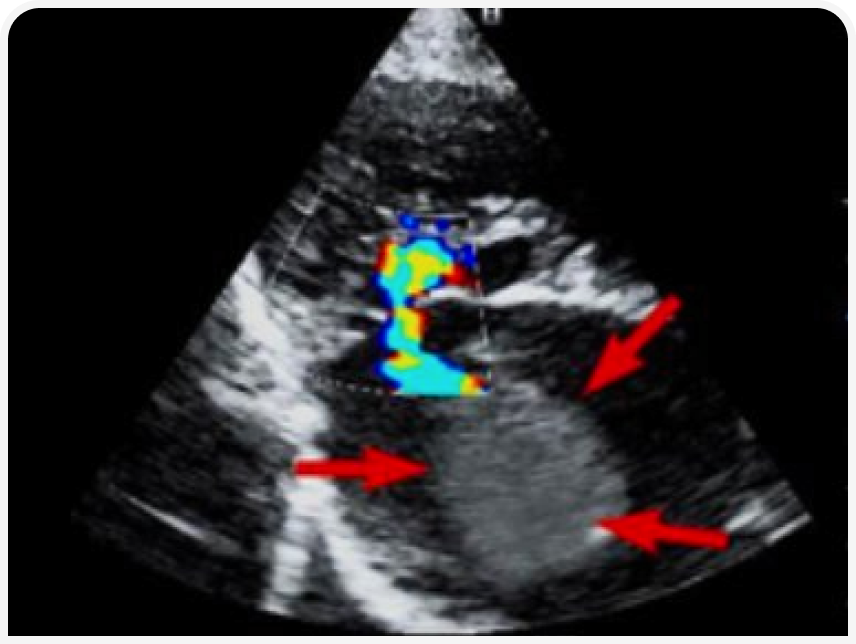

Эхокардиография (рис. 3–5). Данный метод позволяет выявить основное заболевание сердца. Также можно выявить изменение кровотока и замедленное прохождение крови в ушке или в полости левого предсердия посредством импульсно-волнового доплера. У некоторых кошек тромб, формирующийся (в виде облака) или зрелый, можно увидеть в левом предсердии.